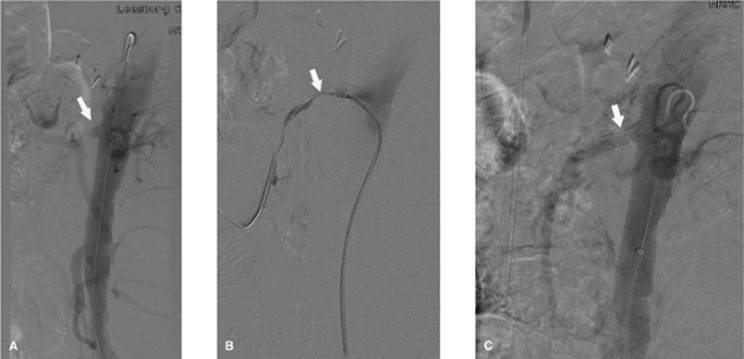

000415

Figure 35.7. A 70-year-old female with progressive pneumothorax following placement of transvenous cardiac pacing device. A: Arrows indicate the partially collapsed left lung following pacing device placement. B: Fluoroscopic image obtained at time of 8 Fr chest tube insertion. The tube was placed slightly lower than the usual apical position to avoid potential damage to the pacing device or wires. C: Following chest tube insertion, the pneumothorax was evacuated with syringe aspiration of the air. Follow-up chest radiograph demonstrates near-completed resolution. The chest tube was connected to Pleur-Evac drainage system.